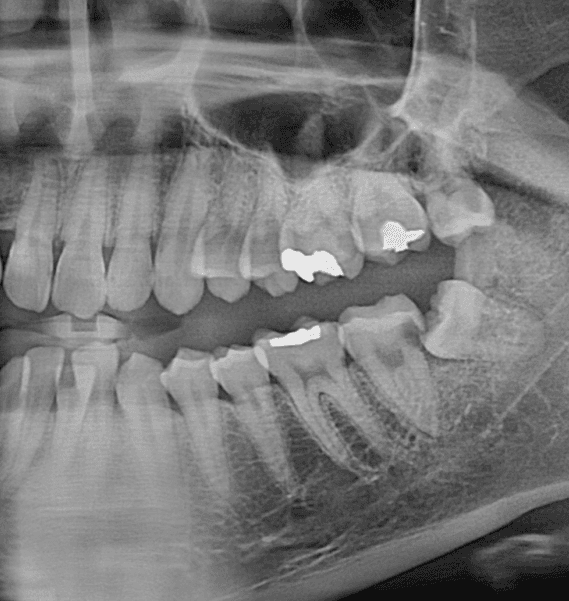

왼쪽 아래 사랑니가 맨 끝 어금니에 충치를 전이시킨 상태라고 하는데요 발치 후 임플란트를 추천하시더라구요

엑스레이상으로 봤을때 임플란트 할 정도로 심각한 상태인건가요?

사랑니로 인해서 앞치에 충치가 많이 생긴 것으로 보입니다. 하지만 앞의 치아에 뿌리는 건강하게 잘 남아 있기 때문에 발치를 한다기보다도 치료를 해서 사용하는 것이 좋습니다. 자세한 확인을 위해서 치과에서 진료를 받아보는 것을 권유드립니다

충치가 깊어 신경치료 및 크라운이 필요한 상황입니다. 발치 후 임플란트 시도하기 전에 치아를 보존해보기를 원하신다면 치과대학병원 치과보존과에 내원하여 상담받아 보세요.

다만 충치자체 양상을 보면 신경치료 후 크라운씌워 살릴 수 있을정도입니다 바로 발치를 해야하는 상황은 아닐것 같습니다

사진이 파노라마라서 명확한 진단은 어렵습니다만 굳이 바로 빼기보다는 신경치료 및 크라운 치료를 통해서 한번 살려볼 수 있어보입니다.